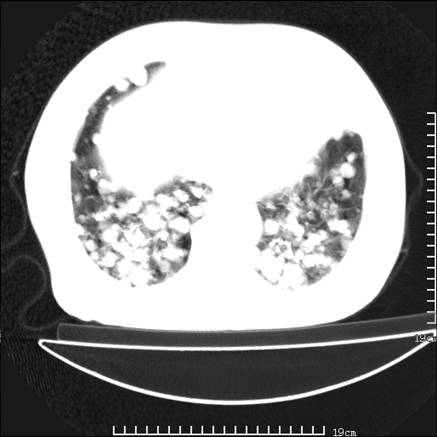

张男,75岁,干咳半年余,小便不利二年,b超检查前列腺增大,未见明显肿块;前列腺癌血生化检查多项指标明显增高。

双肺内多发转移瘤,纵膈淋巴结转移。来源前列腺?建议盆腔mri进一步检查。

双肺转移满了。

两肺广泛转移瘤。